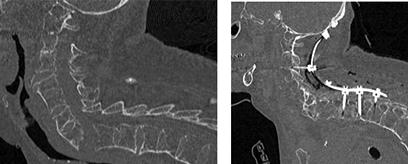

Äldre kvinna som fallit utomhus. Vid fallet hade hon kraftigt nedsatt motorisk funktion i armar och ben. Efter fallet skedde en återhämtning av den motoriska funktionen. Rörelse i halsryggen gav intensiv nacksmärta och samtidig utstrålande smärta i armar och ben. Datortomografi visade degenerativa förändringar i halsryggen utan säker skelettskada. Magnetkamera visade ett prevertebralt ödem mellan C5 och C6, cervikal spinal stenos mellan C5 och C7 och ödem i ryggmärgen. Det prevertebrala ödemet ingav misstanke om genomgående ligamentskador i halsryggen.

Svar: Återhämtning av den motoriska funktionen i detta fall gör att kirurgisk behandling inte behöver göras omedel bart. Tidigare eller pågående neurologisk påverkan är ett mycket allvarligt tecken som indikerar instabilitet i halsryggen. Misstanken om genomgående ligament-

Patient med anamnes på missbruk inneliggande på infektionsavdelning på grund av feber, sjukdomskänsla och högt CRP. Han har också nackvärk och sedan i morse tilltagande svaghet i armar och ben. Magnetkamera visar uttalad prevertebral svullnad, spondylodiskit mellan C5 och C6, och epiduralabscess i halsryggen (pil).

Svar: Progredierande neurologi gör detta till ett mycket akut tillstånd. Patienten ska opereras så fort det är möjligt och oavsett tid på dygnet. Vanligaste tillvägagångssätt vid operation av spondylodiskit och epiduralabscess i halsryggen är främre dekompression och fusion men även bakre dekompression är möjlig.